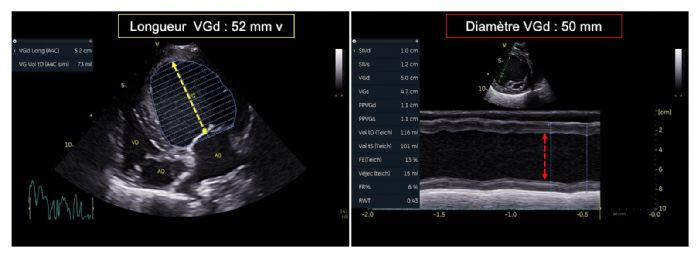

- La diminution de l'indice de sphéricité égale à 1,04 ; (Valeur seuil 1,65 selon Dukes-McEwan et coll., 20032) (Figure 4) ;